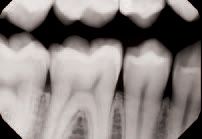

An interproximal lesion was noted on the bitewing on the distal proximal surface of tooth No. 29 (Figs. 3 and 4). The patient was informed of the diagnosis and his options for treatment, which ranged from monitoring the lesion over time to prepping and restoring in a traditional method. We also discussed with him a new technology that fills, reinforces and stabilizes demineralized enamel without removing healthy tooth structure and arrests the progress of the proximal lesion. The patient eagerly opted for the ICON infiltration concept.

Digital x-ray of the lesion on tooth No. 29

(Fig. 4).